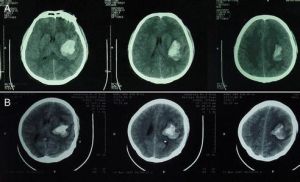

CT檢查:在腦挫裂傷灶附近或腦深部白質內見到圓形或不規則高密度血腫影,有助於確診,同時可見血腫周圍的低密度水腫區。

(1)淺部血腫的出血均來自腦挫裂傷灶,血腫位於傷灶附近或傷灶裂口中,部位多數與腦挫裂傷的好發部位一致,少數與凹陷骨折的部位相應;

(2)深部血腫多見於老年人,血腫位於白質深部,腦的表面可無明顯挫傷。